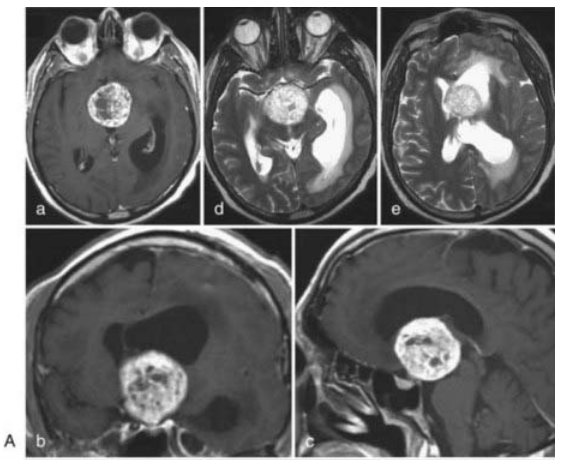

11歲女童,嚴(yán)重視力障礙

術(shù)前MRI(A、B、C)顯示第三腦室內(nèi)富血管實(shí)性腫瘤。經(jīng)右側(cè)聯(lián)合翼點(diǎn)-眶顴開(kāi)顱全切除腫瘤,病理證實(shí)為顱咽管瘤。

術(shù)后早期CT(E、F)示腫瘤全切,患兒術(shù)后僅出現(xiàn)短暫內(nèi)分泌波動(dòng),最終完全康復(fù)。